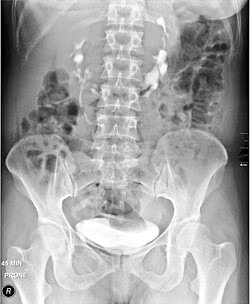

A 19-year-old male presents with recurrent right-sided flank pain and 2 episodes of UTI in the past 1 year. Ultrasound shows bilateral hydronephrosis with a low-lying renal mass crossing the midline anterior to the aorta. CT angiography reveals multiple aberrant renal arteries

A 19-year-old male presents with recurrent right-sided flank pain and 2 episodes of UTI in the past 1 year.

Ultrasound shows bilateral hydronephrosis with a low-lying renal mass crossing the midline anterior to the aorta.

CT angiography reveals multiple aberrant renal arteries